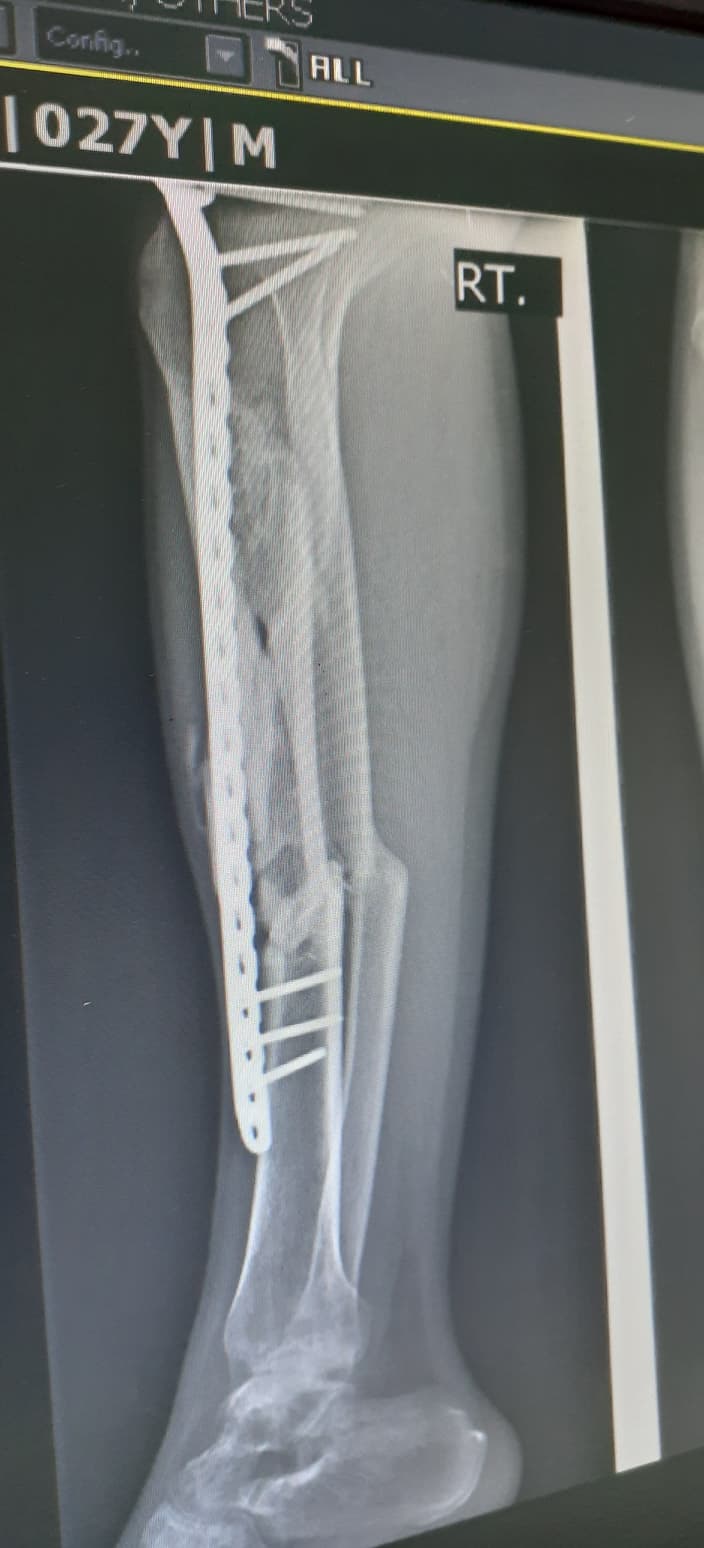

จากภาพเอกซเรย์ที่ปรากฏ หลังจากผ่าตัดมาแล้ว10เดือนครับ คุณหมอให้ลงน้ำหนักได้บ้างโดยการใช้ไม้ค้ำยันเป็นตัวช่วยพยุง แต่แกบอกว่าถ้ามีอาการเสียวให้หยุดเดิน1-2อาทิตย์ตรงนี้หมายความว่าผมสามารถเดินแบบลงน้ำหนักได้ตลอดใช่ไหมครับ (อาการเวลาเดินค่อนข้างจะเจ็บช่วงน่องขามาก)

ภาพข้างล่างหลังจากผ่าตัด4เดือน